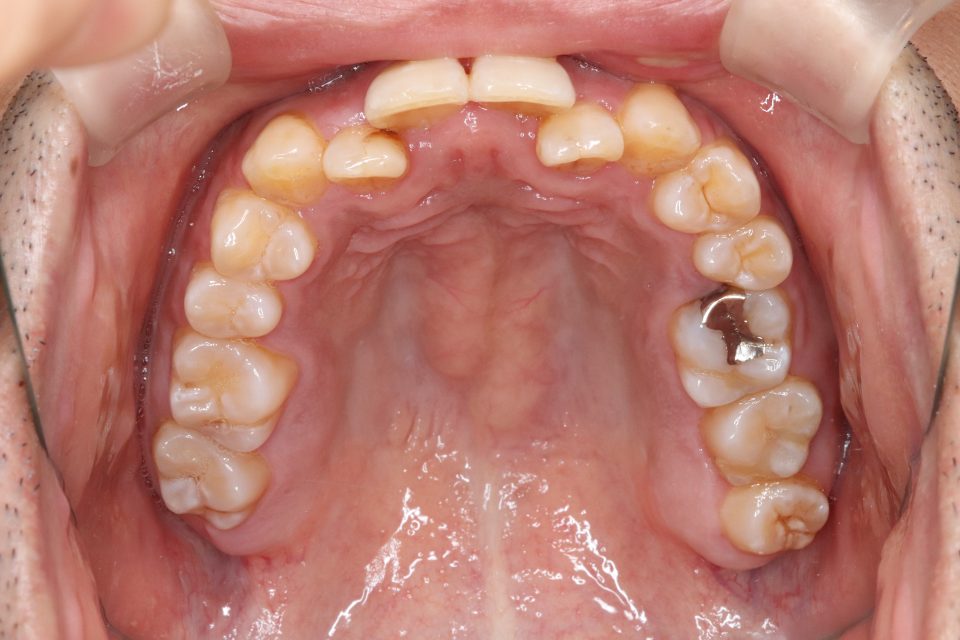

矯正治療前

30代男性です。

歯の凸凹が気になると来院されました。

目立たない装置・取り外し可能なマウスピースタイプでの矯正治療を

希望されてましたのでマウスピース型矯正装置(インビザライン)で矯正治療を行いました。

親知らずを3本抜歯して、歯のやすりがけ(IPR)を行っています。